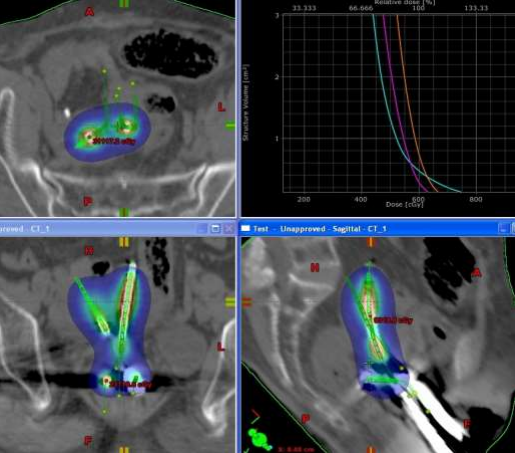

She received the planned EBRT of 50Gy/25# (23# of pelvic irradiation by four field box technique f/b two fractions parametrial boost) in April-May/2022 (last fraction of EBRT on 31/5/22) at a peripheral cancer centre with no brachytherapy facilities. She was referred to our Centre for brachytherapy to complete the treatment. Four fractions of intracavitary brachytherapy two days a week apart, two fractions each day, with a minimum of 6-8 hours between each fraction on each day of brachy delivery (on the 29th of June and the 6th of July 2022). The patient insisted on limited visits because of the long distance from her home. The dose per fraction was 6Gy, and a Fletcher suit with 2.0 cm ovoids was the applicator used for the ICBT. A free tandem(non-dominant) was used in the contralateral cornua, and the dose was optimised to maintain the target and organ at risk constraints. Source loading was done only in the free tandem's distal half to optimise the junctional region's dose.  The free tandem was swapped between the cornua on the two days. Planning was done using Brachyvision Version 8.6, and treatment delivery was done with the Varisource machine (Figures 3, 4 & 5). The EQD2 to the target and OARs (in Gray) were as follows: Tumour (HRCTV)- 80, 2cc of bladder, rectum and sigmoid were 82.8, 74.2 & 78.1 respectively (ABS X-cel sheet was used for EQD2 calculation). At 15 months’ follow-up, the patient is disease-free.

Figure 4: Volume of the Bicornuate uterus with the reconstructed applicators

Figure 5: 6Gy distribution after the optimisation